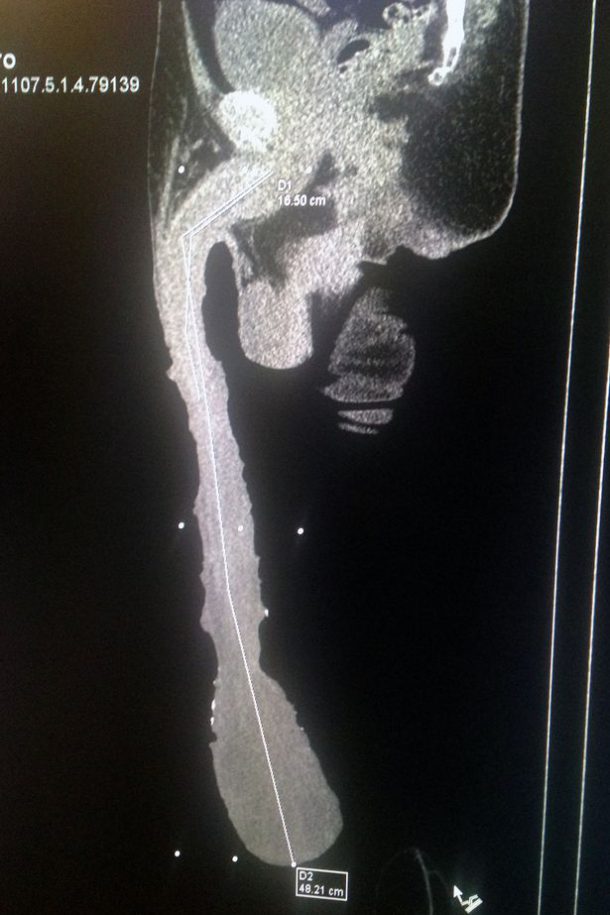

Roberto Esquivel Cabrera, un mexicain âgé de 54 ans, possède le plus gros pénis du monde. D’une taille de 48,21 centimètres pour un poids de 907 grammes, l’homme vit un véritable calvaire. Ses déplacements sont compliqués et la taille de son sexe dissuade les femmes d’avoir des relations sexuelles avec lui.

Malgré ça, Roberto refuse de subir une opération pour réduire la taille de son membre. Il aimerait figurer dans le livre des records mais il y a une subtilité… Selon les médecins qui l’ont examiné, son pénis mesure réellement 15 cm. Les 30 centimètres restants seraient un excédent de peau.